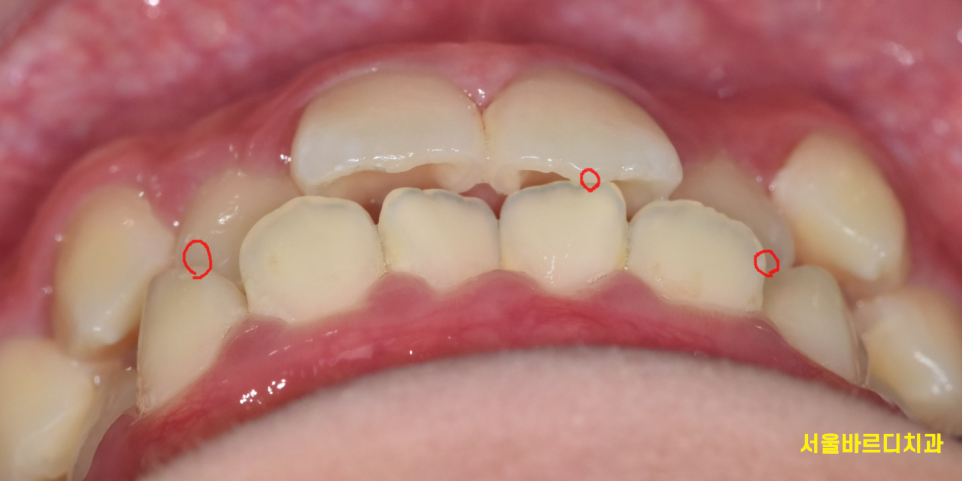

해당 환자분은 또 한가지의 문제가 있었는데요.

송곳니가 기능을 제대로 못하고 계셨습니다.

마치 드라큘라 이빨처럼 굉장히 뾰족 뾰족 하죠?

쉽게 얘기하면 송곳니 덧니입니다.

교과서적으로는 high canine인데

이런 드라큘라 치아를 가지고 있으면

불안정한 교합이 형성됩니다.

약간 어려운 이야기를 할텐데

치아는 위아래로만 씹는게 아닙니다.

옆으로도 운동을 하는데요!

이때 송곳니의 기능이 굉장히 중요해요!!

송곳니는 뿌리가 굉장히 길어서 수명도 길지만

견치유도교합이라 하여

옆으로 가해지는 힘에 다른 치아들을 보호해줄 때

가장 안정적인 교합이라 말합니다.

250120 안닿아야할 치아들이 닿고있어요!